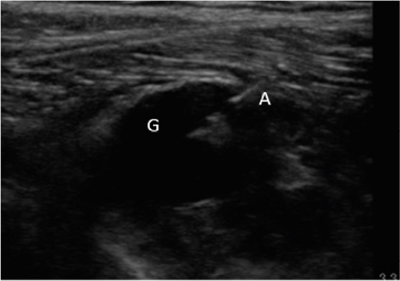

Neuropatía peronea secundaria a ganglión extraneural: revisión de literatura y propuesta de tratamiento. Caso no positivo

Peroneal neuropathy caused by an extraneural ganglion: literary review and treatment proposal. A non-positive case

Este artículo presenta el caso de un paciente de 69 años con una neuropatía compresiva peronea secundaria a un ganglión, inicialmente interpretada como una radiculopatía L5. Este incorrecto enfoque supuso la sobremedicación del paciente, un mal control algésico, la realización de una discectomía L4-L5 innecesaria y una pobre evolución neurológica.

Un enfoque diagnóstico correcto y un abordaje terapéutico precoz habrían supuesto una mayor mejoría clínica e incluso una recuperación neurológica completa del paciente. Por ello, este caso sirve para resaltar: a) el valor de la ecografía en neuropatías periféricas como herramienta diagnóstica y pronóstica y el de la ecografía en gangliones como arma diagnóstico-terapéutica; b) el uso de las pruebas diagnósticas como apoyo a una exploración física exhaustiva, y no como diagnóstico en sí mismas, y c) la importancia de la publicación de casos no positivos para optimizar recursos, evitar repetir errores, reducir el sesgo de publicación y facilitar el inicio de proyectos de investigación.

Tablas y Figuras

Figura 1

Figura 2